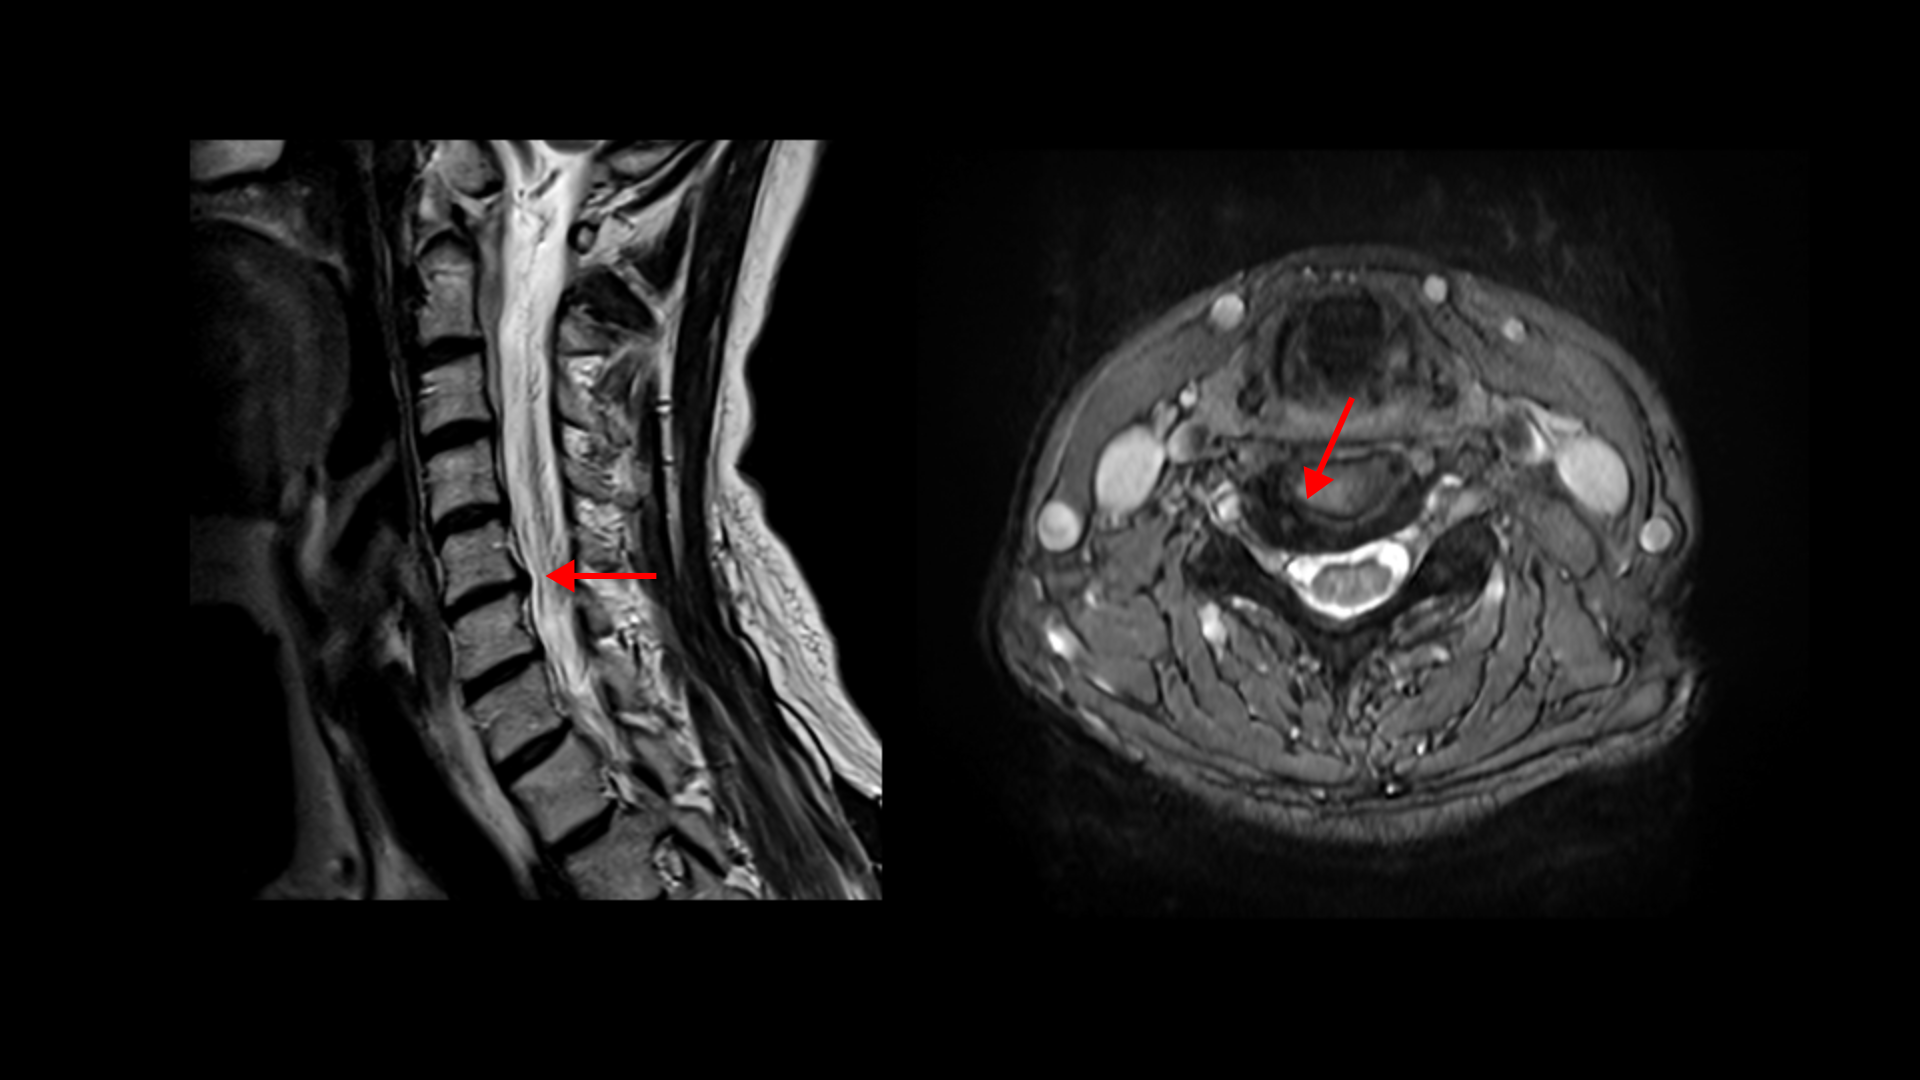

그런데 이런 환자분들이 이런 증상들을 목디스크 증상이라고 알고 계신 분들이 많습니다. 목디스크 연관통이라고요. 그러나 사실은 목디스크 증상이 아닌 별개 증상, 즉 거북목으로 인한 목 앞쪽 근육 단축 및 뭉침으로 인한 증상일 가능성이 높습니다. 목디스크는 우연히도 같이 보이는 겁니다. 실제 이런 증상들이 목디스크 탈출로 인해 생길 수도 있습니다. 급성 목디스크 파열로 인해 극심한 염증성 통증으로 목 근육이 심하게 뭉치면서 이 뭉친 목 근육 때문에 두통, 귀통증, 이명, 돌발성 난청, 어지럼증, 메스꺼움, 눈 통증, 눈 침침함 등이 발생할 수 있습니다. 그런데 이 환자분은 이런 급성 목디스크 탈출로 인해 이런 증상들이 생긴 게 아니고 거북목으로 인해 목 앞쪽 근육이 뭉치고 아프니까 이런 증상들이 발생한 겁니다. 그런데 원인을 알기 위해 MRI검사를 해보면 40대, 50대 이상에서는 원래 퇴행성 목디스크가 많기 때문에 목디스크 탈출이 우연히 보일 가능성이 높은 겁니다. 보시다시피 이분은 목 5번 6번에 퇴행성 디스크가 오른쪽으로 밀려나와 있습니다.

아무튼 이 환자분은 MRI에 목디스크가 밀려나온 게 보이지만 목디스크 증상은 없는 상태였습니다. 그래서 목디스크 증상이 아닌 목 앞쪽 근육 뭉침으로 진단했고, 목 근육 상태를 진찰한 후 뭉쳐있는 목 앞쪽 근육들을 집중적으로 풀어주는 치료를 진행했습니다. 그럼 목 앞쪽 근육 풀어주는 치료로 이 환자분의 증상은 얼마나 빨리 좋아질 수 있을까요? 이분 말씀 먼저 더 들어보겠습니다.